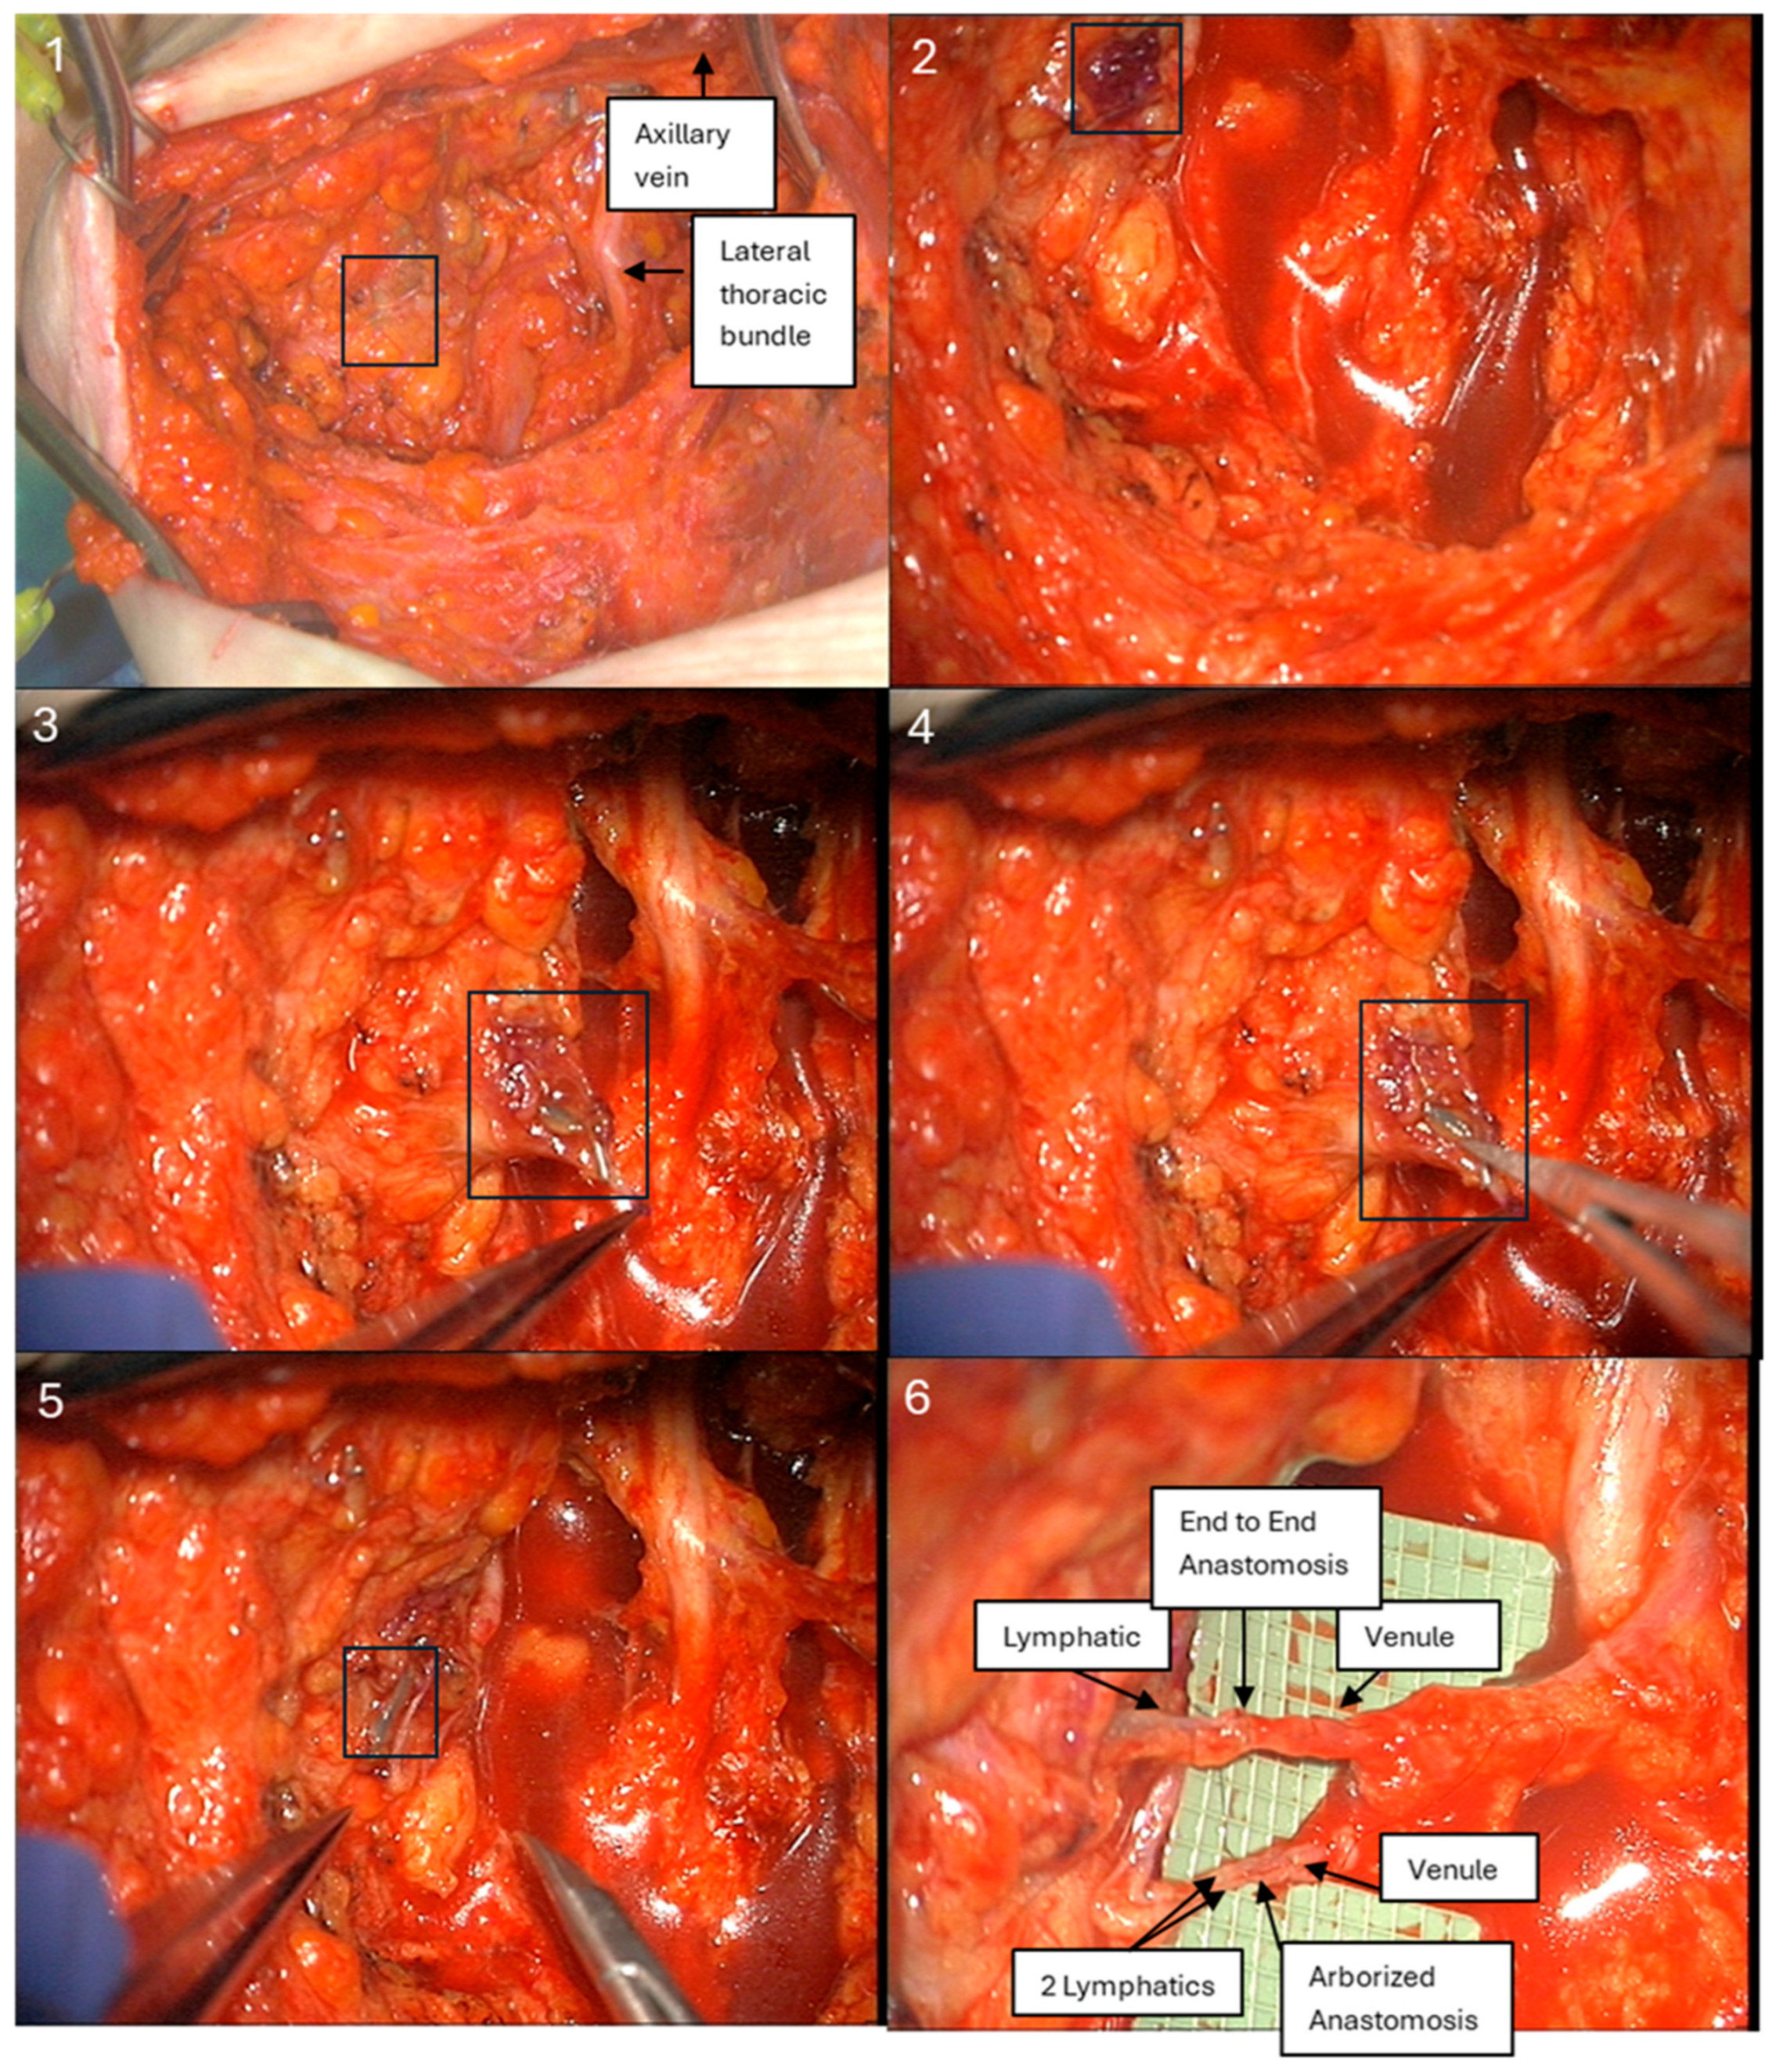

Figure 1. Identifying and tracing the blue-dye-stained lymphatic channel. Successful end-to-end lymphaticovenous anastomosis and arborized lymphaticovenous anastomosis (two lymphatics into one venule).

In this dual-dye ARM series, ICG provided the dominant signal for arm-draining lymphatic channel identification at the time of ALND, both by patient-level visualization rates and by the proportion of channels identified. Baseline clinicopathologic features were largely balanced between dye groups, with the exception of mastectomy type. Visualization with ISB dye showed a non-significant trend toward a greater number of nodes retrieved, while combined-dye visualization did not affect the nodal yield. ILR configuration varied by dye phenotype, with a higher use of arborized anastomoses when both dyes were present, and early lymphedema rates ranged from 10 to 17% across groups (Figure 1). These data support the feasibility of a standardized dual-dye workflow and underscore the practical value of ICG-guided mapping for efficient channel identification and ILR performance.

Following completion of ALND, transected lymphatics and adjacent axillary vein branches amenable to LVB were explored at the same incision site as the axillary dissection, using an operating microscope. ARM lymphatics were visualized as either blue lymphatics or fluorescent during exploration by detecting “hot spots” of leakage, using a near-infrared imaging system (SPY-PHI, Stryker Corporation, Kalamazoo, MI, USA) (Figure 4). LVB was performed by the senior author (D.L.C.) using a surgical microscope (Pentero 800, Carl Zeiss AG, Oberkochen, Germany) with 10-0 nylon sutures (Ethicon, Somerville, NJ, USA) in either an end-to-end or arborized fashion. Intraoperative number, location, and diameter measurements were recorded for all visualized lymphatic vessels stained with either blue dye alone, ICG, or both.